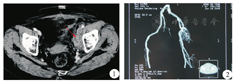

患者女,66岁,因左下肢水肿2月余,2009年6月于汉中市中心医院就诊。患者无腰痛、尿少、血尿、尿痛、尿急、发热、腹痛、腹泻、腹胀、下肢疼痛不适等症状。曾在当地医院检查肾功能未见异常,未治疗。患者左下肢水肿逐渐加重,伴有活动不适及隐痛。查体:体温36.8℃,浅表淋巴结未触及肿大,心肺无异常;腹部稍膨隆,未见腹壁静脉曲张,未见胃肠型和蠕动波,腹部无压痛及反跳痛,腹部未扪及包块。肝脾肋下未触及,肝肾区无叩击痛,移动性浊音阴性,肠鸣音正常。左下肢明显水肿,无溃烂及渗液,皮肤温度及活动正常。肛门指诊:黏膜光滑,未触及肿块,指套染黄色粪迹。实验室检查:血常规、尿常规、肝功、肾功、电解质、血脂等均正常。入院后盆腔增强CT显示左侧盆腔可见4.3 cm×2.4 cm混杂低密度影包绕髂外动脉,与血管间界限不清(图1),考虑肿瘤占位。考虑左髂静脉受肿瘤侵犯致管腔狭窄静脉血回流不畅所致,予行血管造影证实(图2)。盆腔肿块穿刺病理检查:可能为软组织黄色肉芽肿。手术探查术中见腹内无腹水,肝、胆囊、脾、大小网膜、小肠及其系膜、结肠及其系膜表面,胃前壁腹膜等腹内脏器未见明显肿瘤转移结节,腹主动脉旁及肠系膜上血管根部无肿大淋巴结。肿瘤位于左侧盆腔侧后壁,大小为10.0 cm×5.0 cm×2.0 cm,不规则,肿块质地硬,固定,边界不清,包裹髂内动静脉,肿块固定无法切除。术中肿块穿刺活检示:可见大量肿瘤细胞呈泡沫样,细胞间有纤维组织和血管增生,有较多异型的上皮细胞和梭形细胞。病理诊断为黄色肉芽肿。术后16 d行三维立体适型放射治疗,设四野照射,照射剂量为PCTV:2 Gy/次,5次/周,连续5周。2009年8月初放射治疗结束后,复查盆腔CT显示:左侧髂窝肿块较前缩小,病变大小约为2.1 cm×1.8 cm(图3)。Recist标准疗效评级部分缓解。6个月后,左下肢水肿逐渐消退,复查盆腔CT显示:左侧髂窝肿块较前无增大,遂植入血管扩张支架1枚,左下肢水肿逐渐完全消退,并多次复查盆腔CT,2017年10月初CT提示病灶仍稳定,左侧髂窝肿块完全消退,并可见金属支架影(图4)。3~6个月复查1次,目前已随访8年余,病情稳定,患者生活完全能自理,继续随访中。